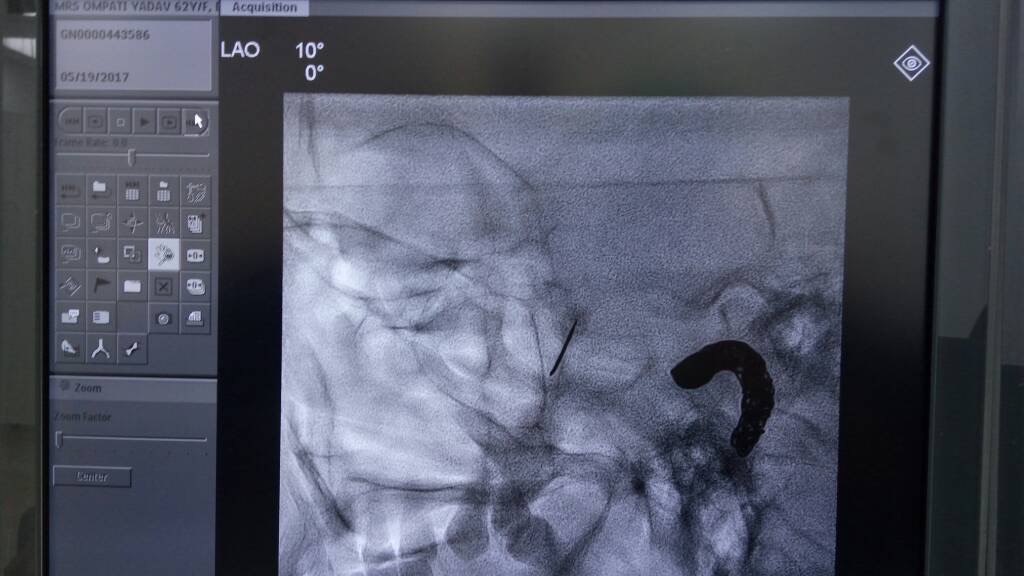

The patient is usually sedated, and using X-ray (fluoroscopy) guidance, a fine needle is placed near the SPG and anesthetic is injected. The patient will not feel numbness in the face. Pain relief may also not be immediate. If pain relief is good with local anesthetic but for a few days or weeks we do a radiofrequency ablation of SPG or neurolysis for long lasting pain relief.